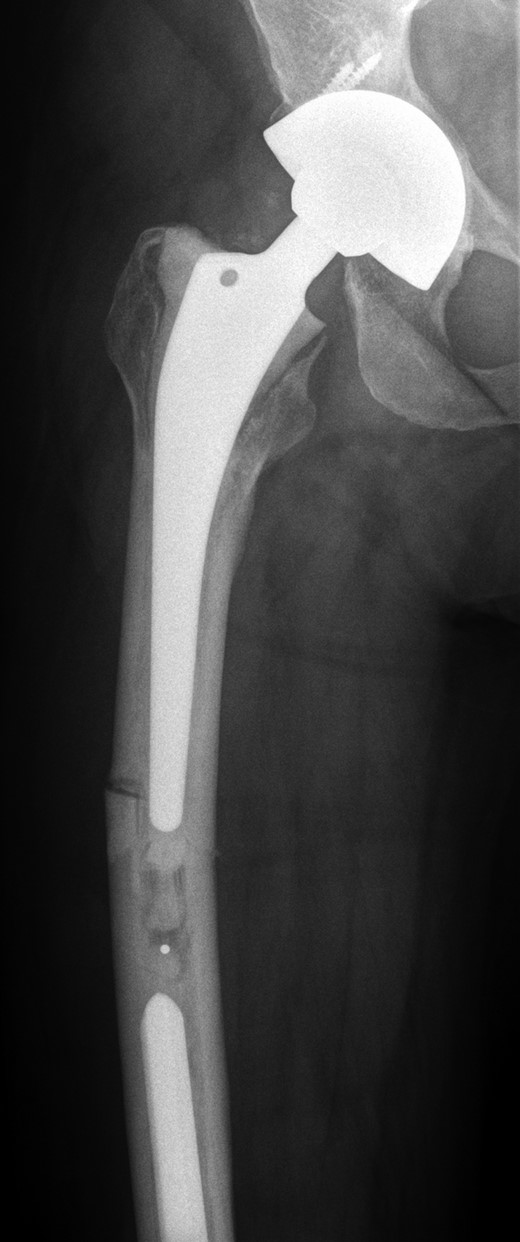

She subsequently sustained a periprosthetic fracture at the distal tip of her right total hip replacement (Fig. 1). An initial attempt was made to manage this fracture with a plate and Dall-Miles cables (Fig. 2); however, the fracture did not unite. The patient went on to have a custom-made cement-linked internal proximal femoral replacement, which had a hollow cylindrical design to accept the stem of the existing well-fixed distal femoral component (Figs 3 and 4). This linked prosthesis effectively converted her separate prostheses to a total femoral replacement, sparing her distal femoral replacement from revision. She had no problems postoperatively and recovered well from her surgery.

Periprosthetic fracture distal tip of right total hip replacement.